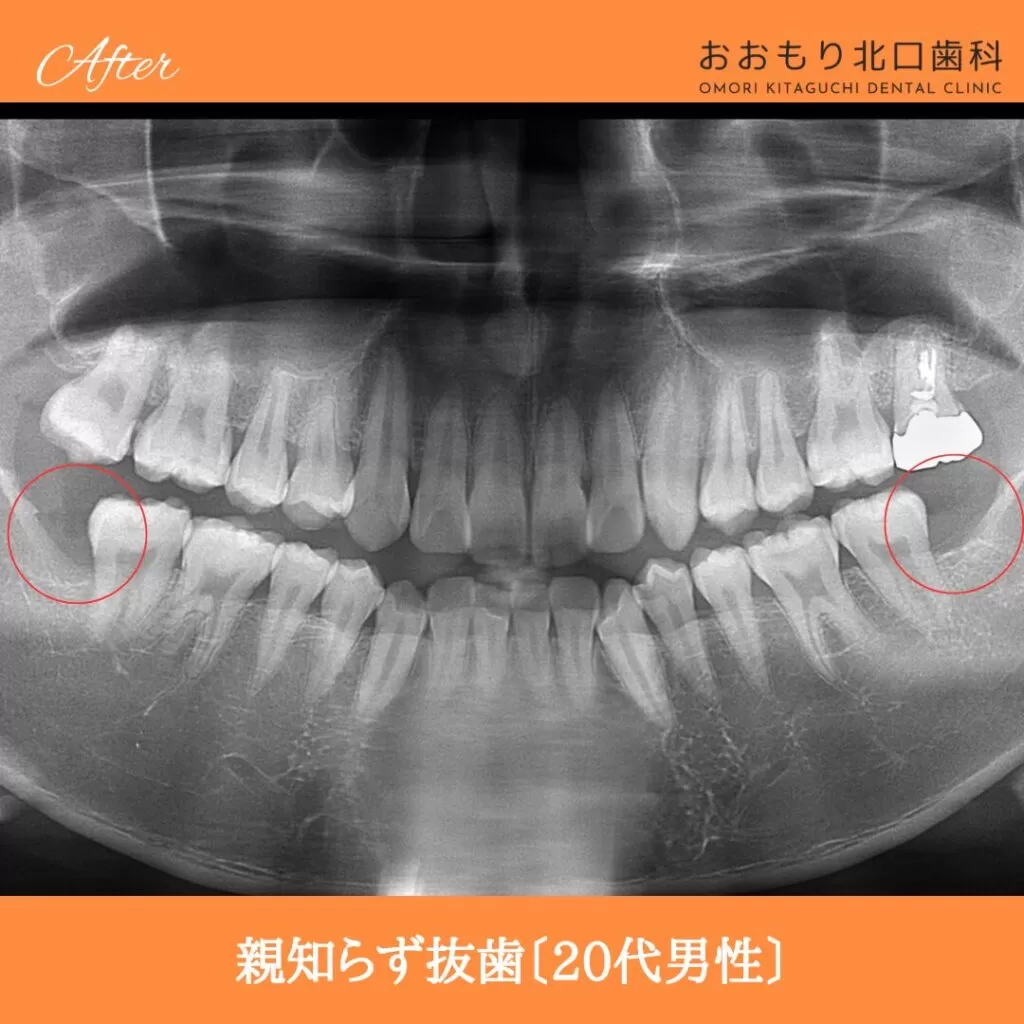

症例紹介㊷親知らず抜歯(20代男性)

本日は「親知らず抜歯」を行われた患者さまのビフォーアフターをご紹介します。

【治療名】親知らず抜歯

【患者さん】20代男性

【費用(税込)】保険治療

【リスク】 親知らずの抜歯は、手術中は麻酔により痛みを感じることがほとんどありません。

しかし、麻酔が切れた後には、時には腫れや痛みが発生することがあります。